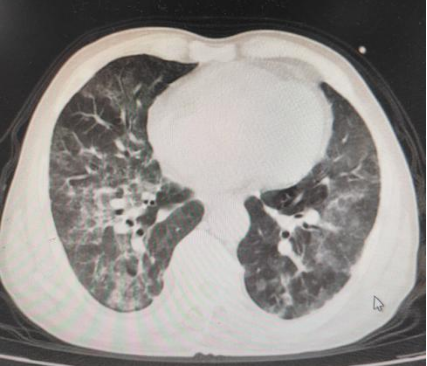

胸部CT平扫(2025.10.21):

患者于2025年10月21日停止高流量吸氧,改为鼻导管吸氧,22日从ICU转入普通病房继续治疗。